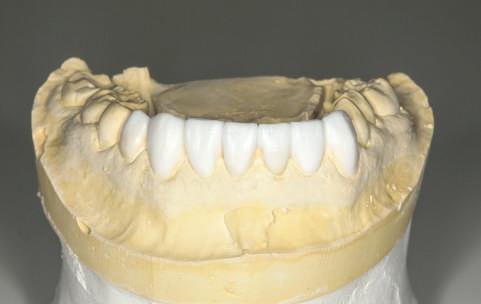

Raţiunea asigurării unei armonii biologice este completată de criterii tehnice ce ghidează laboratorul în cursul fabricării unei restaurări dentare estetice şi funcţionale. Totuşi, ceea ce nu se înţelege întotdeauna în laborator este faptul că limitările anatomice oferă adesea cea mai mare valoare predictivă pentru integrarea estetică a unei restaurări implantare anterioare.

Pentru a maximiza estetica restaurărilor implantare frontale, etapa iniţială a planului de tratament include integrarea protezei în zâmbetul pacientului, în conformitate cu limitările anatomice ale pacientului.

Acest articol examinează rolul bontului în susţinerea succesului estetic şi tehnic. Sunt incluse discuţii cu privire la restaurările cimentate vs fixate cu şurub, selecţia materialului pentru substituţia dintelui frontal şi parametrii designului.

Dacă însă implanturile sunt plasate prea vestibular sau prea superficial, componentele nu permit un design adecvat al bontului, pentru că plasarea marginii este limitată iar conturul facial şi proximal poate fi compromis (fig. 1, 2).

Deşi în acest articol sunt prezentate criteriile pentru fabricarea bontului implantar, este important de menţionat că integrarea zâmbetului pacientului este determinantă înainte de inserarea implantului, iar rolul bontului

în susţinerea esteticii este limitat de procesul de planificare a tratamentului pentru restaurarea finală (fig. 3-5).